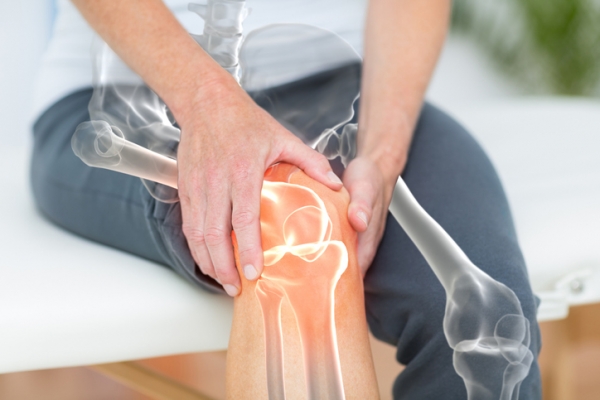

퇴행성 관절염은 관절을 보호하고 있는 연골이 손상되거나 퇴행하는 질환으로, 나이가 들면서 늘어나는 흔한 질환입니다.

퇴행성 관절염은 뼈와 인대에 염증과 통증을 일으키고, 관절의 기능을 저하시키며, 관절의 변형을 초래할 수 있습니다.

1. 관절의 통증

퇴행성 관절염의 가장 대표적인 증상으로, 관절을 움직일 때나 휴식을 취할 때도 통증을 느낄 수 있습니다.

통증은 점점 심해지고, 날씨가 추울 때나 습할 때에는 더 심하게 느껴질 수 있습니다.